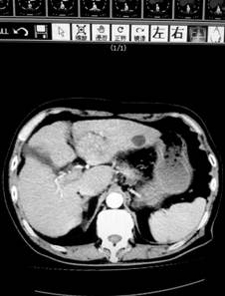

上午9點(diǎn),第一肝門預(yù)阻斷后,肝臟手術(shù)正式開(kāi)始,患者是一位80歲的肝癌患者,腫瘤位于肝左葉,合并肝炎并肝硬化,考慮患者肝功能較差,依據(jù)腫瘤根治原則,為患者成功實(shí)施了左肝外葉切除。目前該患者正在進(jìn)一步康復(fù)。